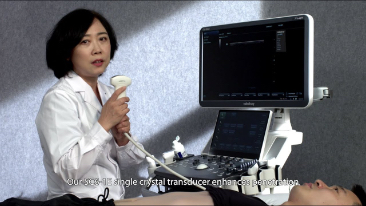

Mindray? ??? ??? ?? ??? ???? ??? ?? ??? ??? ????? ??? ????. ?? ???? ZONE Sonography? ??? ???? ?? Resona 7? ??? ZST+ ???? ?? ?? ? ?? ??? ????? ?? ??? ??? ??? ? ?? ????.

?? Resona 7? ???? ??? ?? ???? ??? ??? ???? ??? ?? ???? V Flow? ?? CNS ??? ?? 3D ??? ???? ?? ???? ?? ??? ?? ?? ?? ??? ??????. ???? ??? ??? ?? ?? ??? ??? ?? ?? ??? ??? Resona 7? ??? ???? ???? ??? ??? ??? ????.